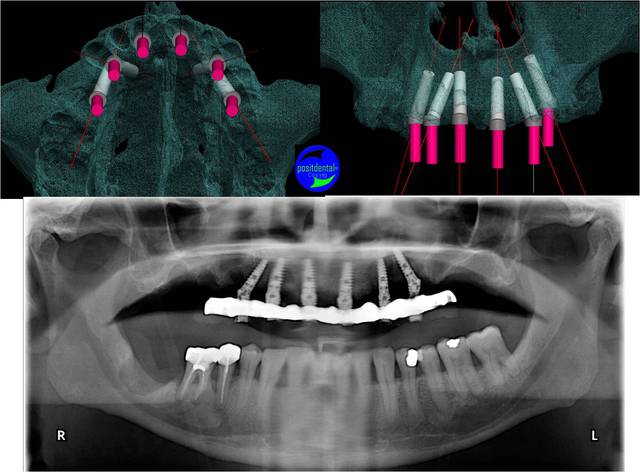

Castor la position de l’apex de l’implant angulé est aussi importante pour laisser un volume osseux pour les implants mésiaux. Sur cet exemple il était important de le placer pré de la corticale palatine vestibulaire.la densité rencontrait fait que tu n’as spécialement une corticale sur laquelle t’appuyer.

Tu peux voir que les angulations planifiées sont correctement reproduites.